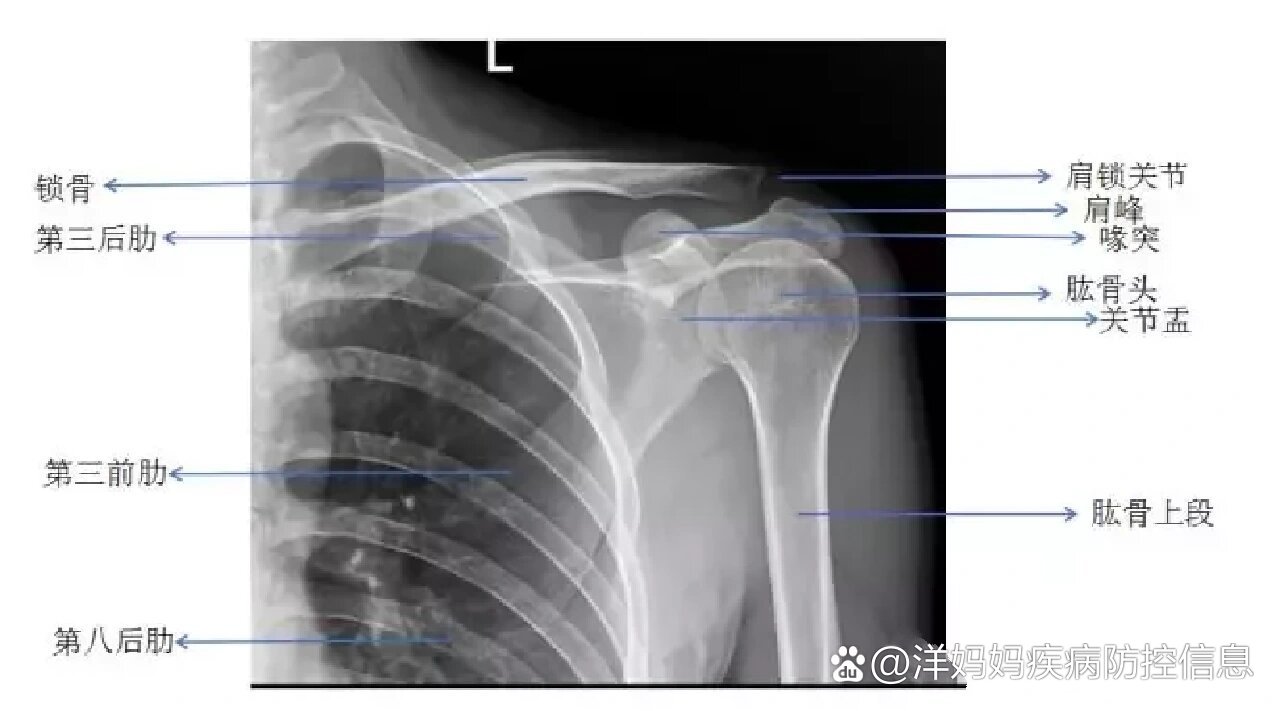

正常肩关节x片

x线检查:肩关节正位,侧位片显示肩关节骨质未见明显异常,排

解剖回顾:肩关节x线解剖讲解,初学者收藏!